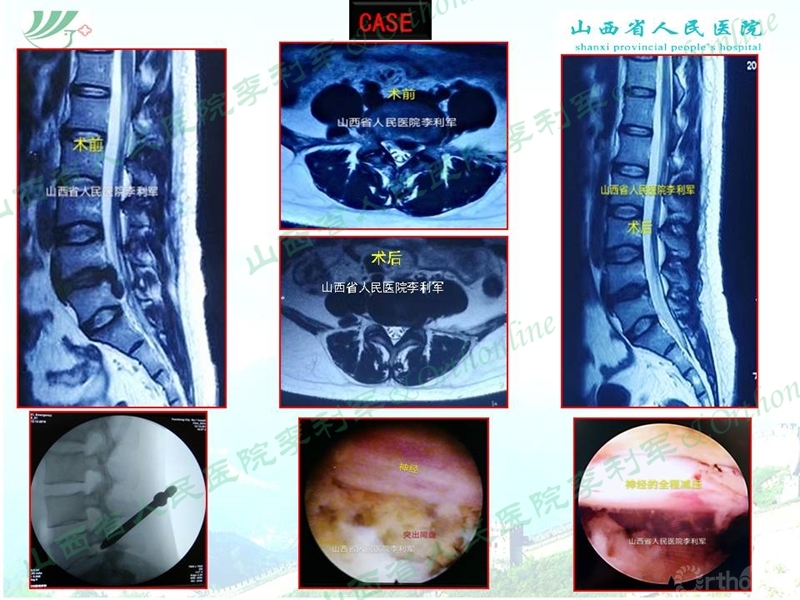

椎间孔镜技术治疗腰椎间盘突出症目前已经是一项比较成熟的技术,对于普通的腰椎间盘突出症的治疗来讲,利用常规的穿刺、置管及镜下操作都可以顺利完成手术,但我们在临床上会遇到一些不典型的、特殊类型的腰椎间盘突出,单纯按照常规技巧去做,可能会遇到一些棘手的问题,导致手术难以顺利完成,甚至出现某些并发症。

山西省人民医院李利军医生根据自己临床遇到的部分病例,归纳常见的特殊腰椎间盘突出为:高度游离间盘突出,伴有钙化的间盘突出,巨大间盘突出,复发间盘,极外侧间盘突出,易误诊为肿瘤的间盘突出,伴有神经变异的间盘突出等;并根据自己的临床体会对以上特殊类型间盘突出的孔镜治疗作了一些技术总结,以期达到抛砖引玉的作用,并等到大家的批评和指导。